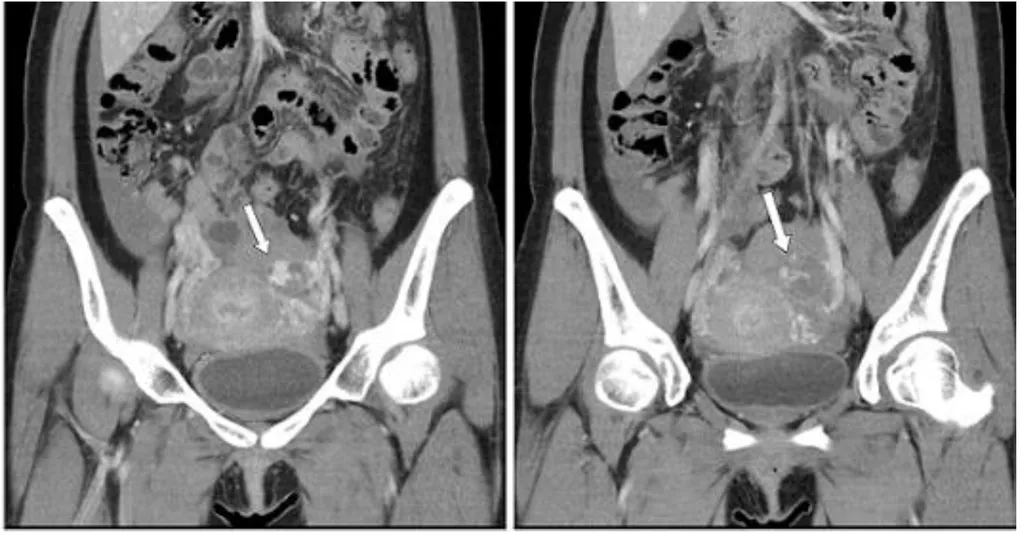

【114-1 醫學(六) 第73題】28 歲女性主訴腹部突然劇痛,注射顯影劑後電腦斷層檢查呈現如圖,箭號所指之病灶,下列何項診斷最不可能?

這張電腦斷層影像顯示骨盆腔內有大量高密度液體(血液)和一個不規則的病灶,這代表病人正經歷急性且嚴重的腹腔內出血,因此要找出最不可能導致這種「急性大出血」的診斷。